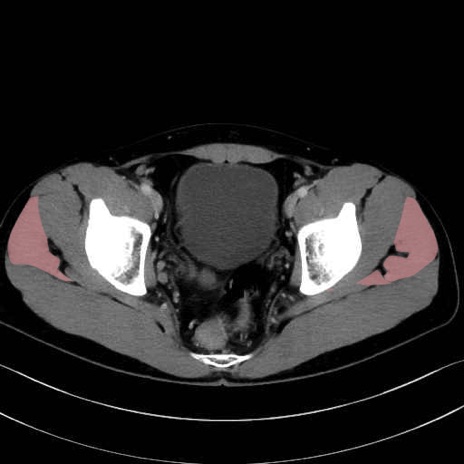

中殿筋 (Gluteus medius)